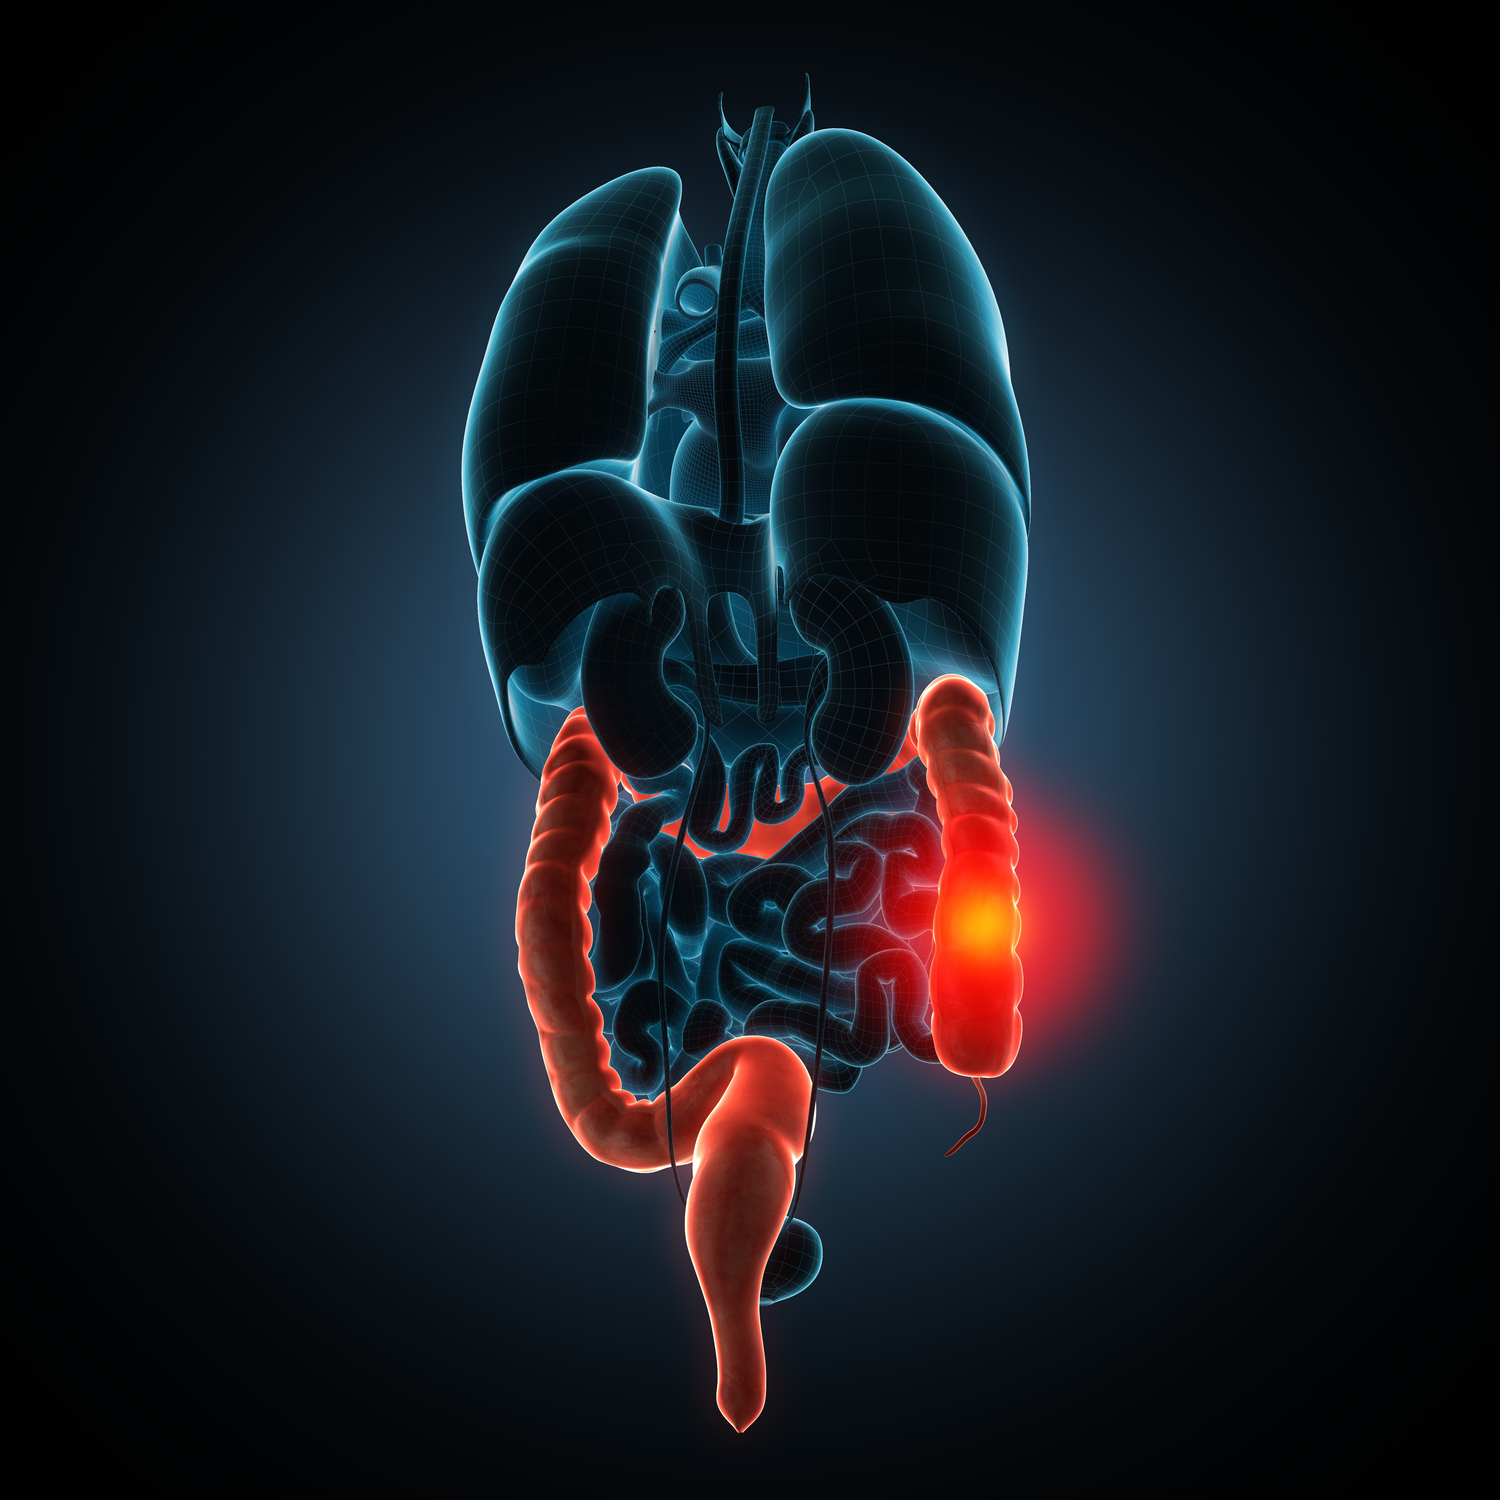

Crohn’s Disease Common Signs and Symptoms

Crohn’s disease is a chronic inflammatory bowel disease that results in the inflammation of the gastrointestinal (GI) tract, which extends from the mouth to the anus. The disease can affect any part of the GI tract. A combination of hereditary, immune, and environmental factors results in the development of this chronic inflammatory disorder.